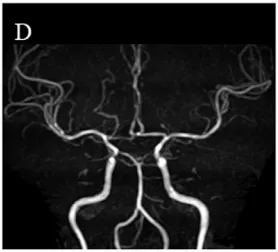

但是这位女性头部除了不规则的颅内动脉壁,MRI并没有显示烟雾病的(图1D),也从未经历过短暂的或永久性的神经系统症状。